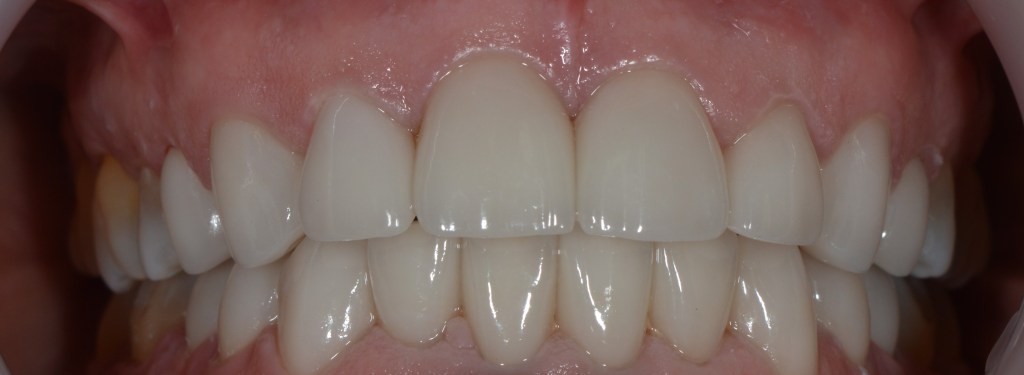

Kozmetikai és funkcionális kezelés: felső torlódott fogak kiegyenesítése, koronák enyhe kifele döntése, mélyharapás korrigálása.

A választott korona típusa: CAD/CAM (komputer vezérelt tervezés/megmunkálás) technológiával készült cirkónium (fémmentes) szóló koronák.

A választott fogszín: A2

A protetikai munka elkészülésének ideje: 5 munkanap.